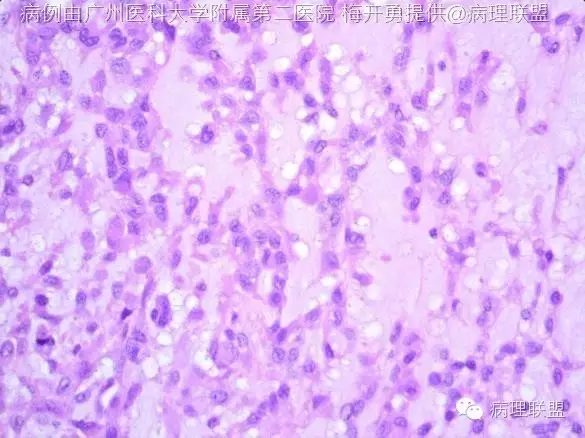

肿瘤位于支气管黏膜下,瘤细胞呈短梭形细胞、卵圆形细胞、多边形细胞和星状细胞,弥漫排列或呈条索状排列,间质呈黏液样。瘤细胞显示有一定的异型性,可见核分裂。形态学类似肌上皮肿瘤或骨外粘液性软骨肉瘤。